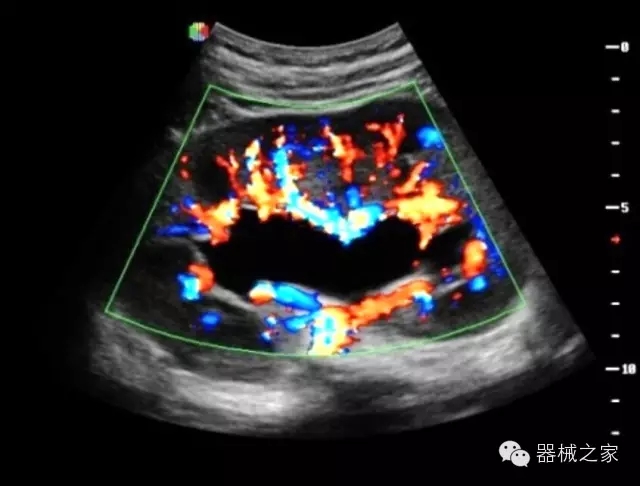

臨床圖片賞析

·獨(dú)有的RF平臺(tái)提高微小細(xì)節(jié)顯示、圖像對(duì)比度和邊界清晰度;

·特有的XCEN探頭,超寬的帶寬,表現(xiàn)更高分辨率和對(duì)比度;

·單晶純凈波探頭提供更佳的穿透力和彩色敏感度;

·完整的3D/4D臨床應(yīng)用,STIC, MCUT 和Auto NT等滿足產(chǎn)科所有應(yīng)用;

·更高的HQ羊膜腔鏡成像技術(shù)精細(xì)觀察每一個(gè)暗區(qū)細(xì)節(jié);

·獨(dú)有RF敏感血流使得心臟血流完美呈現(xiàn);